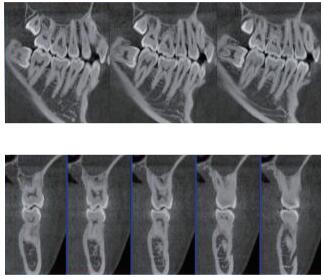

三維重建任意斷層

專有三維重建算法,可提供任意位置高清斷層影像。

高清口腔全景影像

通過三維容積影像,提取高清口腔全景影像。

多平面組合重建

可同時觀察軸向面、冠狀面和矢狀面圖像,方便臨床診斷。